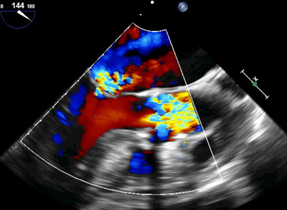

近日,华中科技大学同济医学院附属协和医院心脏大血管外科启动佰仁医疗Salus介入肺动脉瓣临床试验入组,并于当天成功完成1例经胸介入肺动脉瓣植入,获得了理想的治疗效果。

近日,四川大学华西医院心脏大血管外科安琪教授团队与心脏内科冯沅教授团队联合启动佰仁医疗Salus介入肺动脉瓣临床试验入组,并于当天成功完成1例经胸小切口介入肺动脉瓣植入,获得了理想的治疗效果。

2022年7月23日,武汉大学中南医院亚洲精品视频中文字幕免费看中心张刚成、刘金平教授团队正式启动佰仁医疗Salus介入肺动脉瓣临床试验入组,并于当天与阜外华中心血管病医院范太兵教授团队合作成功完成1例经胸介入肺动脉瓣植入,该研究由首都医科大学附属北京安贞医院牵头,联合多家知名心脏中心参与,是国内首个经胸介入肺动脉瓣临床试验,具有重大意义。